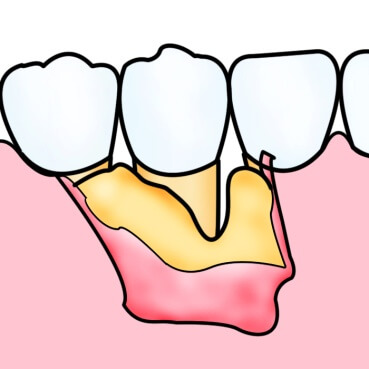

歯周病の進行により、歯を支えている骨は溶けてしまいます。通常、一度失った骨は元に戻りませんが、ケースによっては再生療法によって骨の回復が可能となります。また、平成28年9月に、厚生労働省より承認を受け、最近、保険導入された、歯周組織再生剤「リグロス®」の使用も行っております。(その他にもいくつかの方法があります。)

歯周病によって失ってしまった歯周組織部位に、歯周組織再生剤を塗布することで骨組織を再生させます。